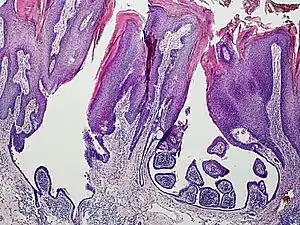

Syringocystadenoma papilliferum

Syringocystadenoma papilliferum is a benign apocrine tumor.[1]

An example of a syringocystadenoma papilliferum